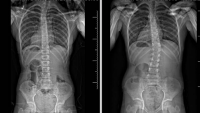

Due to a genetic disorder, Zoe’s scoliosis was more fragilely cared for than most. When it came time for surgery, having a doctor liked Dr. Michael Vitale that the Schimmels could trust was crucial.

Angela was diagnosed with Infantile Idiopathic Scoliosis when she was only seven months old, learn more about her journey with Dr. Vitale over the last six years.

When the curve in Zara’s spine started progressing quickly, her family turned to Dr. Michael Vitale at Columbia Orthopedics for a conservative care approach for her scoliosis.